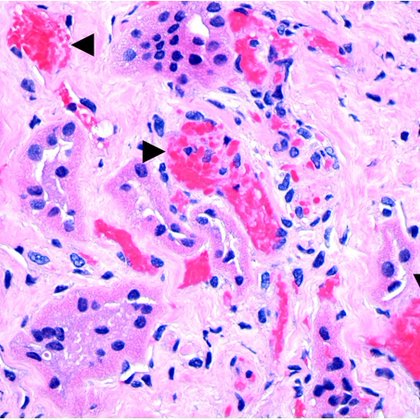

The paucity of tubular profiles in the renal medulla should raise the consideration of a hemoglobinopathy, especially in those with African ancestry, such as this patient. Notably, the cortex has much less tubular loss. RBC sickling occurs in the medulla where it's more hypoxic